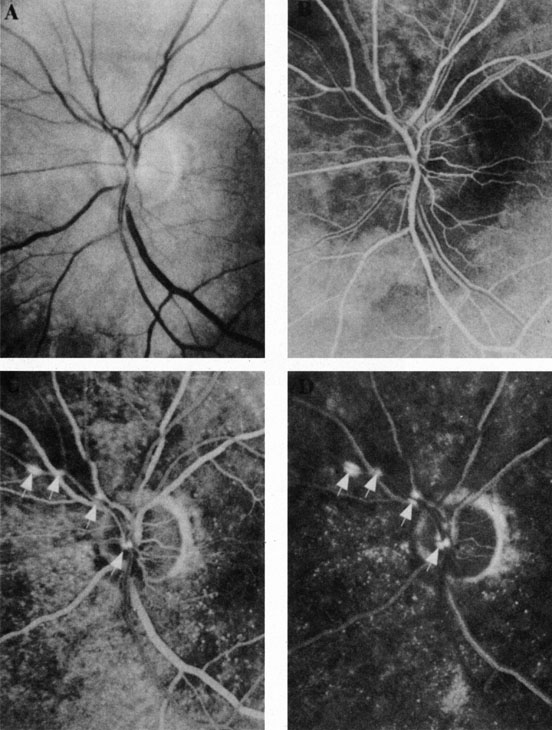

The clinical picture is typically striking. Patients present with a sudden painless loss of vision. The appearance of a cherry-red spot in the fundus is characteristic (Fig. 1).2 The cherry-red spot appears because soon after obstruction of the blood flow to the inner retina, the normally transparent retina becomes opaque and blocks the brownish-red color from the underlying choroid, which is still supplied by blood. Because the retina overlying the foveola is relatively thin, however, the normal color of the choroid is still visible in this area.3,4 Although characteristic, the cherry-red spot is not pathognomonic for central retina artery obstruction.5 Sometimes the characteristic cherry-red spot does not develop; there may be only a slight accentuation of the brownish-red color in the foveola.4 It is not known how long it takes this cherry-red spot to appear, but in a primate model, it has appeared as early as 30 minutes after obstruction.6 An afferent pupil defect is usually present.2

With time, the retinal opacity diminishes, generally leaving an optic nerve that is atrophic (Fig. 1). Frequently, thinned retinal arteries and veins also remain.7,8 No foveolar light reflex is evident, and a finely pigmented appearance of the macula is typical.7 In some cases, arterial collaterals develop at the optic disc.9–11 Rarely, anatomoses that exist between the central retinal artery and the ciliary arteries become visible as preretinal loops (Nettleship collaterals) after an occlusion at the edge of the disc.12,13,378In approximately 20% of patients, an embolus is evident somewhere in the arterial system.14 Emboli are discussed later.

Intravenous fluorescein angiography is useful in showing the details of the abnormal circulation of a central retinal artery obstruction (Fig. 1). The principal abnormality is the delay in the appearance of the dye in the central retinal artery and its branches.2 Rather than the central retinal artery and its branches filling rapidly, considerable time may elapse before the entire arterial system is filled.15 The filling of the retinal arteries is often abnormal, with the fluorescein partially filling an artery (a dye front) or hugging the vessel wall, as in normal venous filling.15

Optic coherence tomography (OCT) of an acute central retinal artery occlusion shows a slight increase in the thickening of the retina and reflectivity of the inner layers of the retina that correspond to the opacity seen clinically (Fig. 1).409 With time, the disc becomes atrophic and the retina thinner.